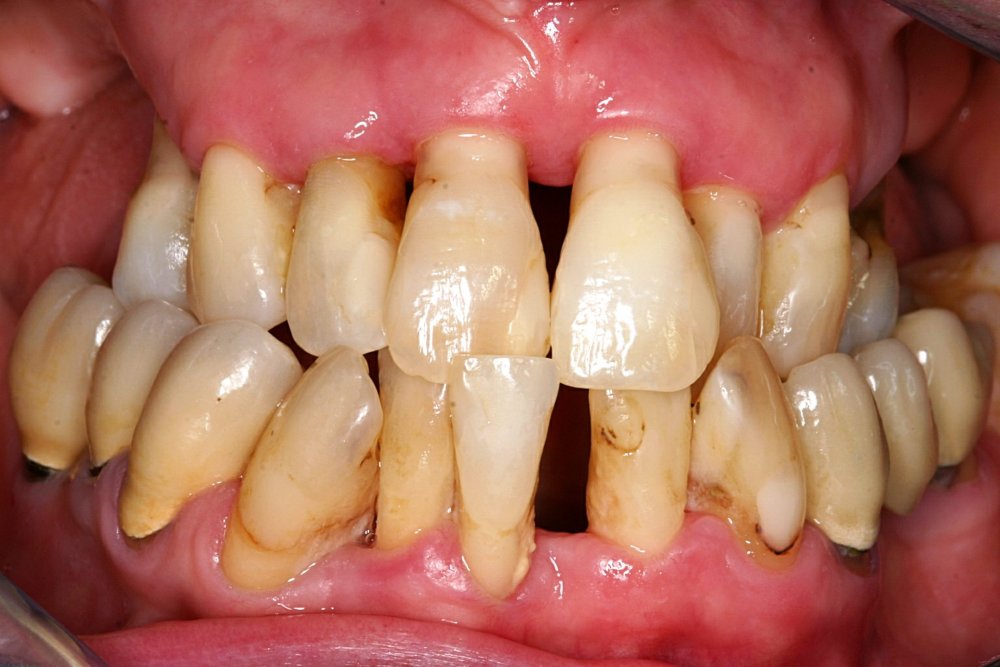

Qeyri-cərrahi parodontoloji müalicədən sonra bəzi hallarda, bu və ya digər bölgədə dərin parodontal ciblər (diş əti və sümük cibi) qalmaqda davam edir. Bu hallarda çox zaman müalicə cərrahi metodların tətbiqi ilə davam etdirilir. Bu zaman əsas məqsəd mövcud parodontal cibin bu və ya digər metodlarda aradan qaldırılmasını təmin etməkdir.

Çünki bu ciblər çox zaman pasiyent tərəfindən yetərincə təmizlənə bilmir. Bu isə həmin bölgəyə tədricən ərp və dolayısı ilə də bakteriya koloniyalarının toplanmasına səbəb olur. Bu proses yenidən yerli iltihabın ortaya çıxmasına səbəb olur. Tətbiq edilən cərrahi metodlar əsasən cibin yerləşdiyi diş bölgəsi, cibin eni, dərinliyi, konfiqurasiyası və s. xüsusiyyətlərə görə müəyyənləşdirilir. Bu zaman məqsəd mümkün olduqda həmin bölgədə bərpa prosedurunu həyata keçirmək, mümkün olmadıqda isə rezektiv müalicənin tətbiqi ilə həmin bölgəyə ərp toplanma ehtimalını azaltmaq və gigiyenik prosedurların icrasını pasiyent üçün rahatlaşdırmaqdır.

Rezektiv prosedurlar zamanı müəyyən miqdarda yumuşaq toxuma (diş əti), sərt toxuma (sümük) və ya kombinə olunmuş şəkildə (həm sümük, həm də yumuşaq toxuma) rezeksiya həyata keçirilir. Prosedur yerli ağrısızlaşdırma altında aparılır. Əməliyyatdan sonrakı dövrdə fərdi qulluq və gigiyena qaydalarının mötəxəssis tərəfindən izahı və müvafiq instruksiyanın verilməsi olduqca önəmlidir.